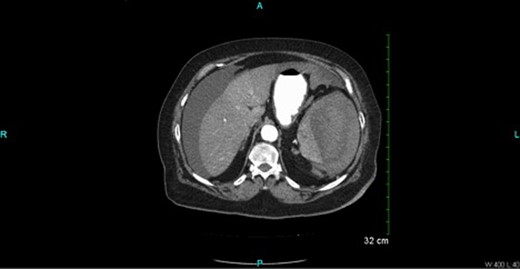

CT scan (Figs 2 and 3) revealed a large hematoma at the lateral margin of the spleen that displaced the spleen medially and compresses its lateral margin. A moderate amount of relatively low attenuation fluid also tracked into the right paracolic gutter and perihepatic space. There also appeared to be a 3.5 × 2.5 cm broad-based mass along the wall of the right colon. The CT scan of the chest also demonstrated a pulmonary embolus in a subsegmental artery of the right upper lobe. Given these findings, the patient was aggressively resuscitated with packed red blood cells and taken emergently to the operating theatre.

Oral and intravenous contrast enhanced CT of the abdomen demonstrating air within the colonic lumen and a 3.5 × 2.5 cm broad-based mass along the wall of the right colon (white arrow).